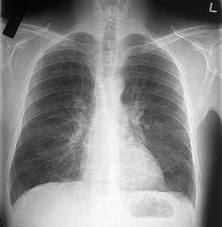

Диагностика острого бронхита не требует сложных методов исследования и может быть осуществлена на основе жалоб больного и данных полученных при осмотре и обследовании больного. Больному проводят рентгенологическое исследование легких, исследование функции внешнего дыхания, клинический анализ крови.

Медицинские процедуры, проводимые при заболевании бронхит: Рентгенография легких, Клинический анализ крови, Функция внешнего дыхания, ЭКГ, Бронхоскопия, Радиоизотопное исследование